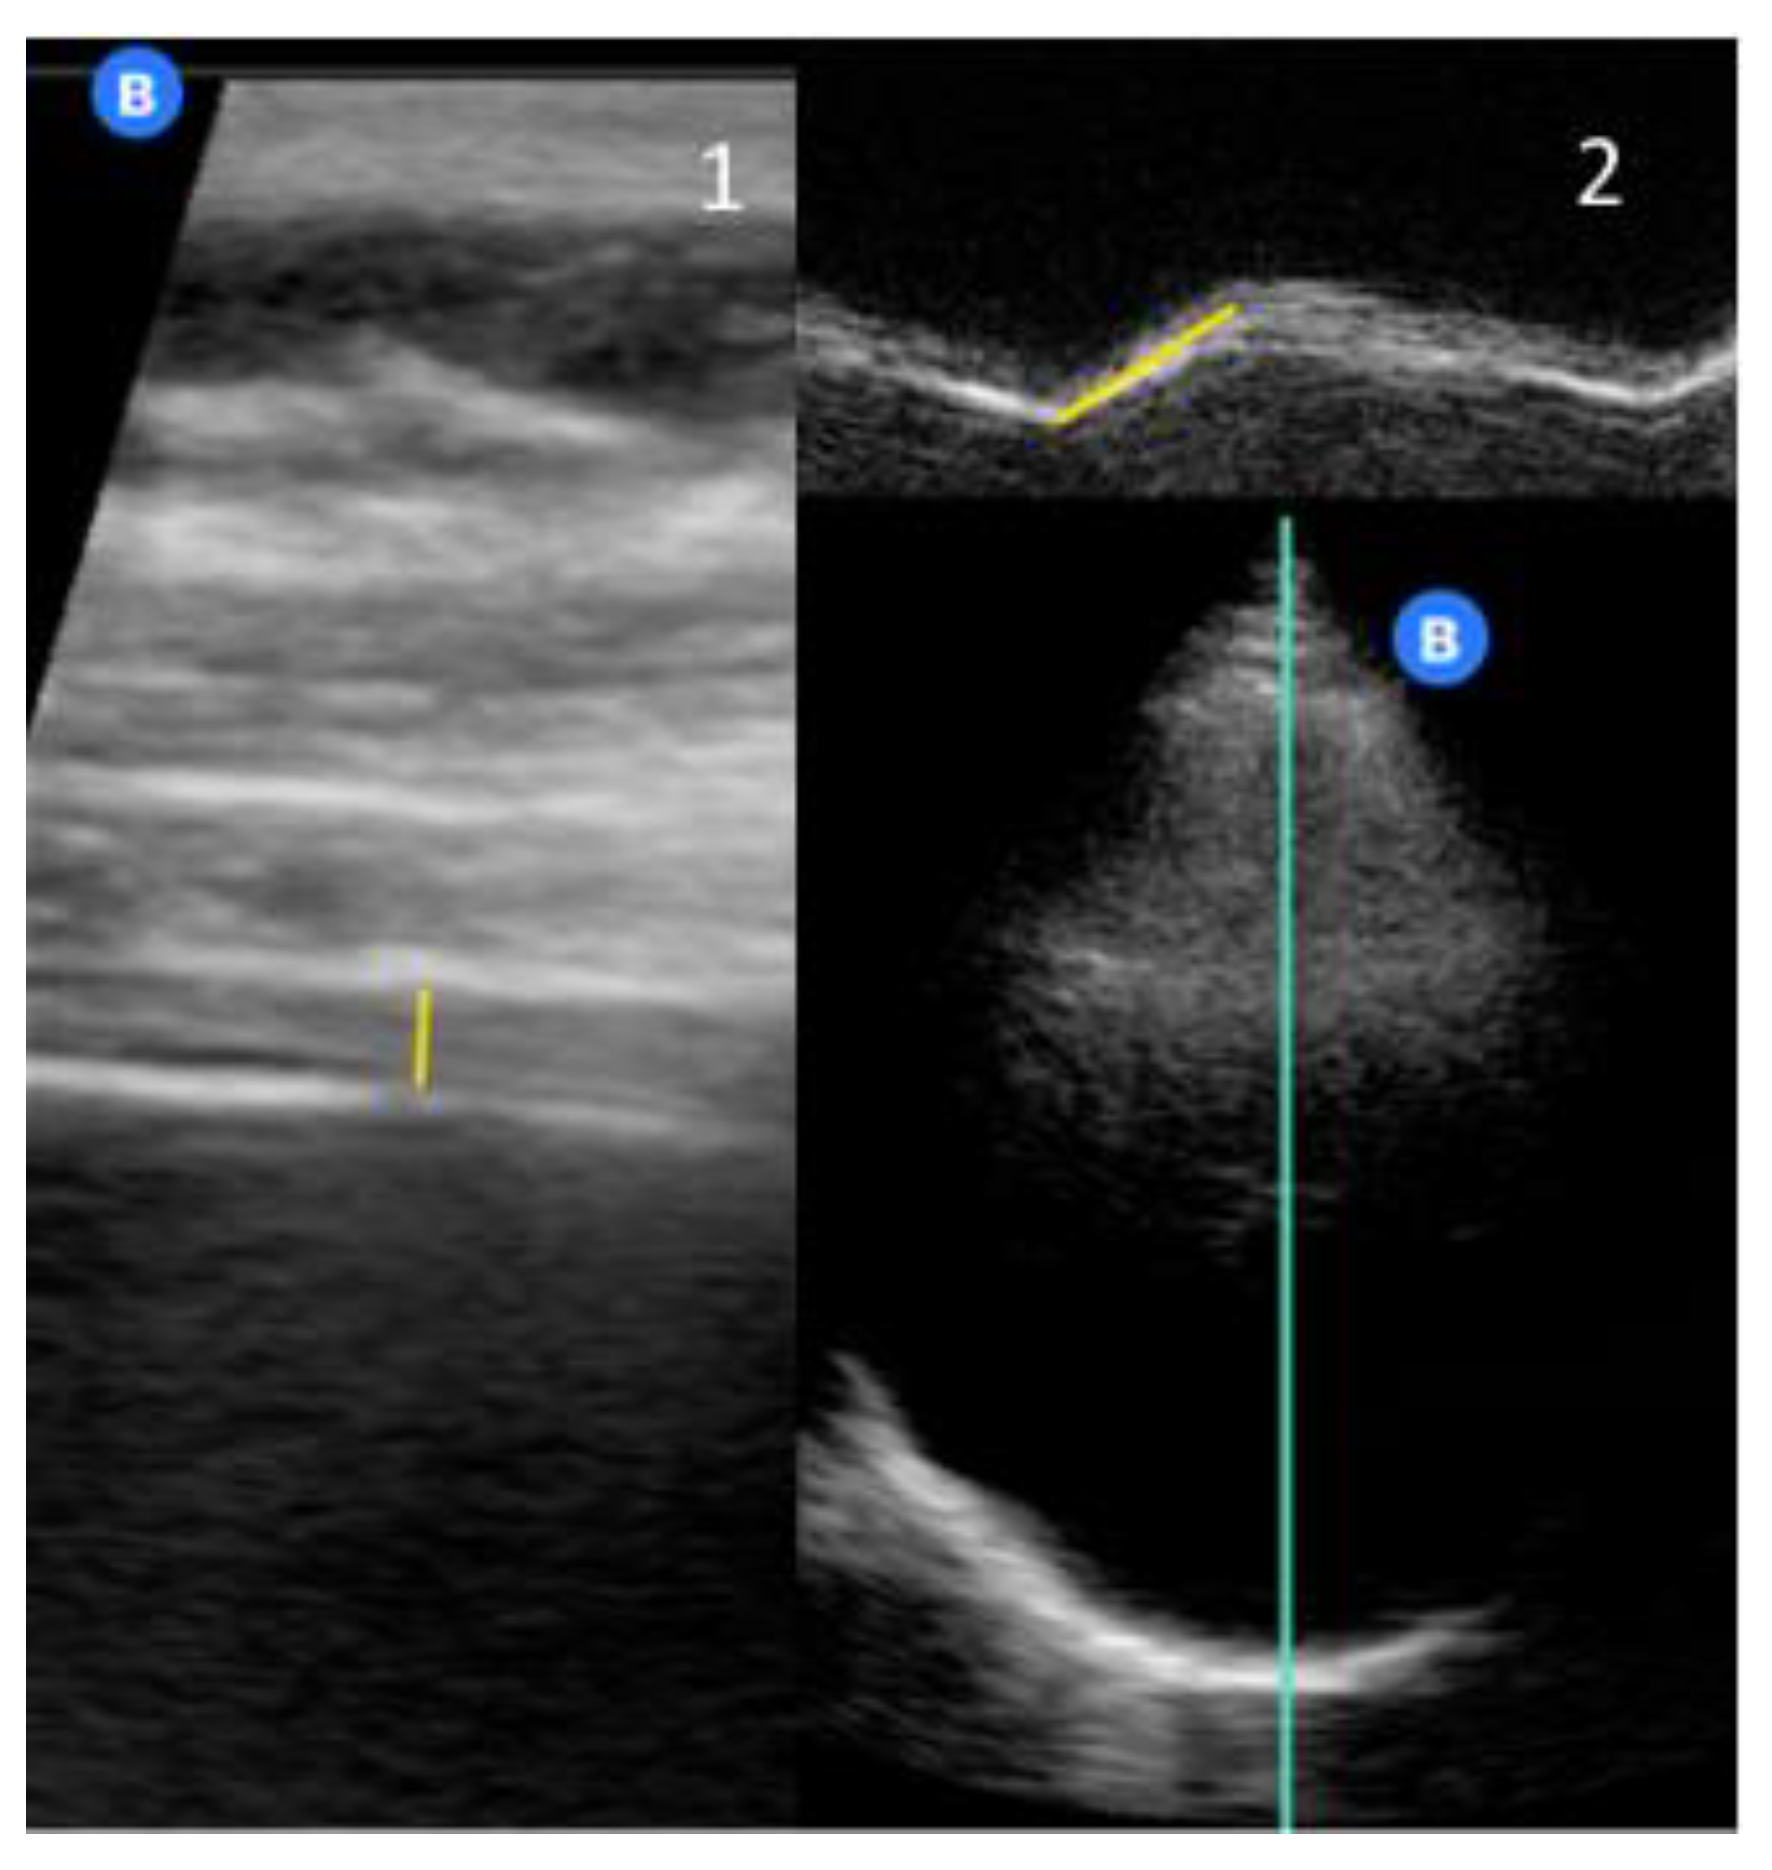

Ultrasound image of the zone of apposition of the diaphragm. In Diaphragm Function Using Ultrasound The main goals of diaphragm ultrasound in critically ill patients are: Ultrasound measurements of diaphragm thickness have been used to identify diaphragm atrophy. Functional imaging with fluoroscopy (or ultrasonography or magnetic resonance imaging) is a simple and effective method of diagnosing diaphragmatic. Assessment of diaphragm function over time:. Comparison to phrenic stimulation and prognostic implications Diaphragmatic ultrasound has gained importance. Diaphragm Function Using Ultrasound.

Assessment of the right hemi diaphragm motion from the subcostal view Diaphragm Function Using Ultrasound Ultrasound evaluation of diaphragm function in mechanically ventilated patients: This chapter focuses on thoracic ultrasound as a noninvasive technique for diaphragm morphological and functional. Comparison to phrenic stimulation and prognostic implications Functional imaging with fluoroscopy (or ultrasonography or magnetic resonance imaging) is a simple and effective method of diagnosing diaphragmatic. The main goals of diaphragm ultrasound in critically ill patients. Diaphragm Function Using Ultrasound.

Diaphragmatic excursion measured by an ultrasound system. (A) Tidal Diaphragm Function Using Ultrasound Comparison to phrenic stimulation and prognostic implications The main goals of diaphragm ultrasound in critically ill patients are: Assessment of diaphragm function over time:. Functional imaging with fluoroscopy (or ultrasonography or magnetic resonance imaging) is a simple and effective method of diagnosing diaphragmatic. This chapter focuses on thoracic ultrasound as a noninvasive technique for diaphragm morphological and functional. Ultrasound measurements. Diaphragm Function Using Ultrasound.